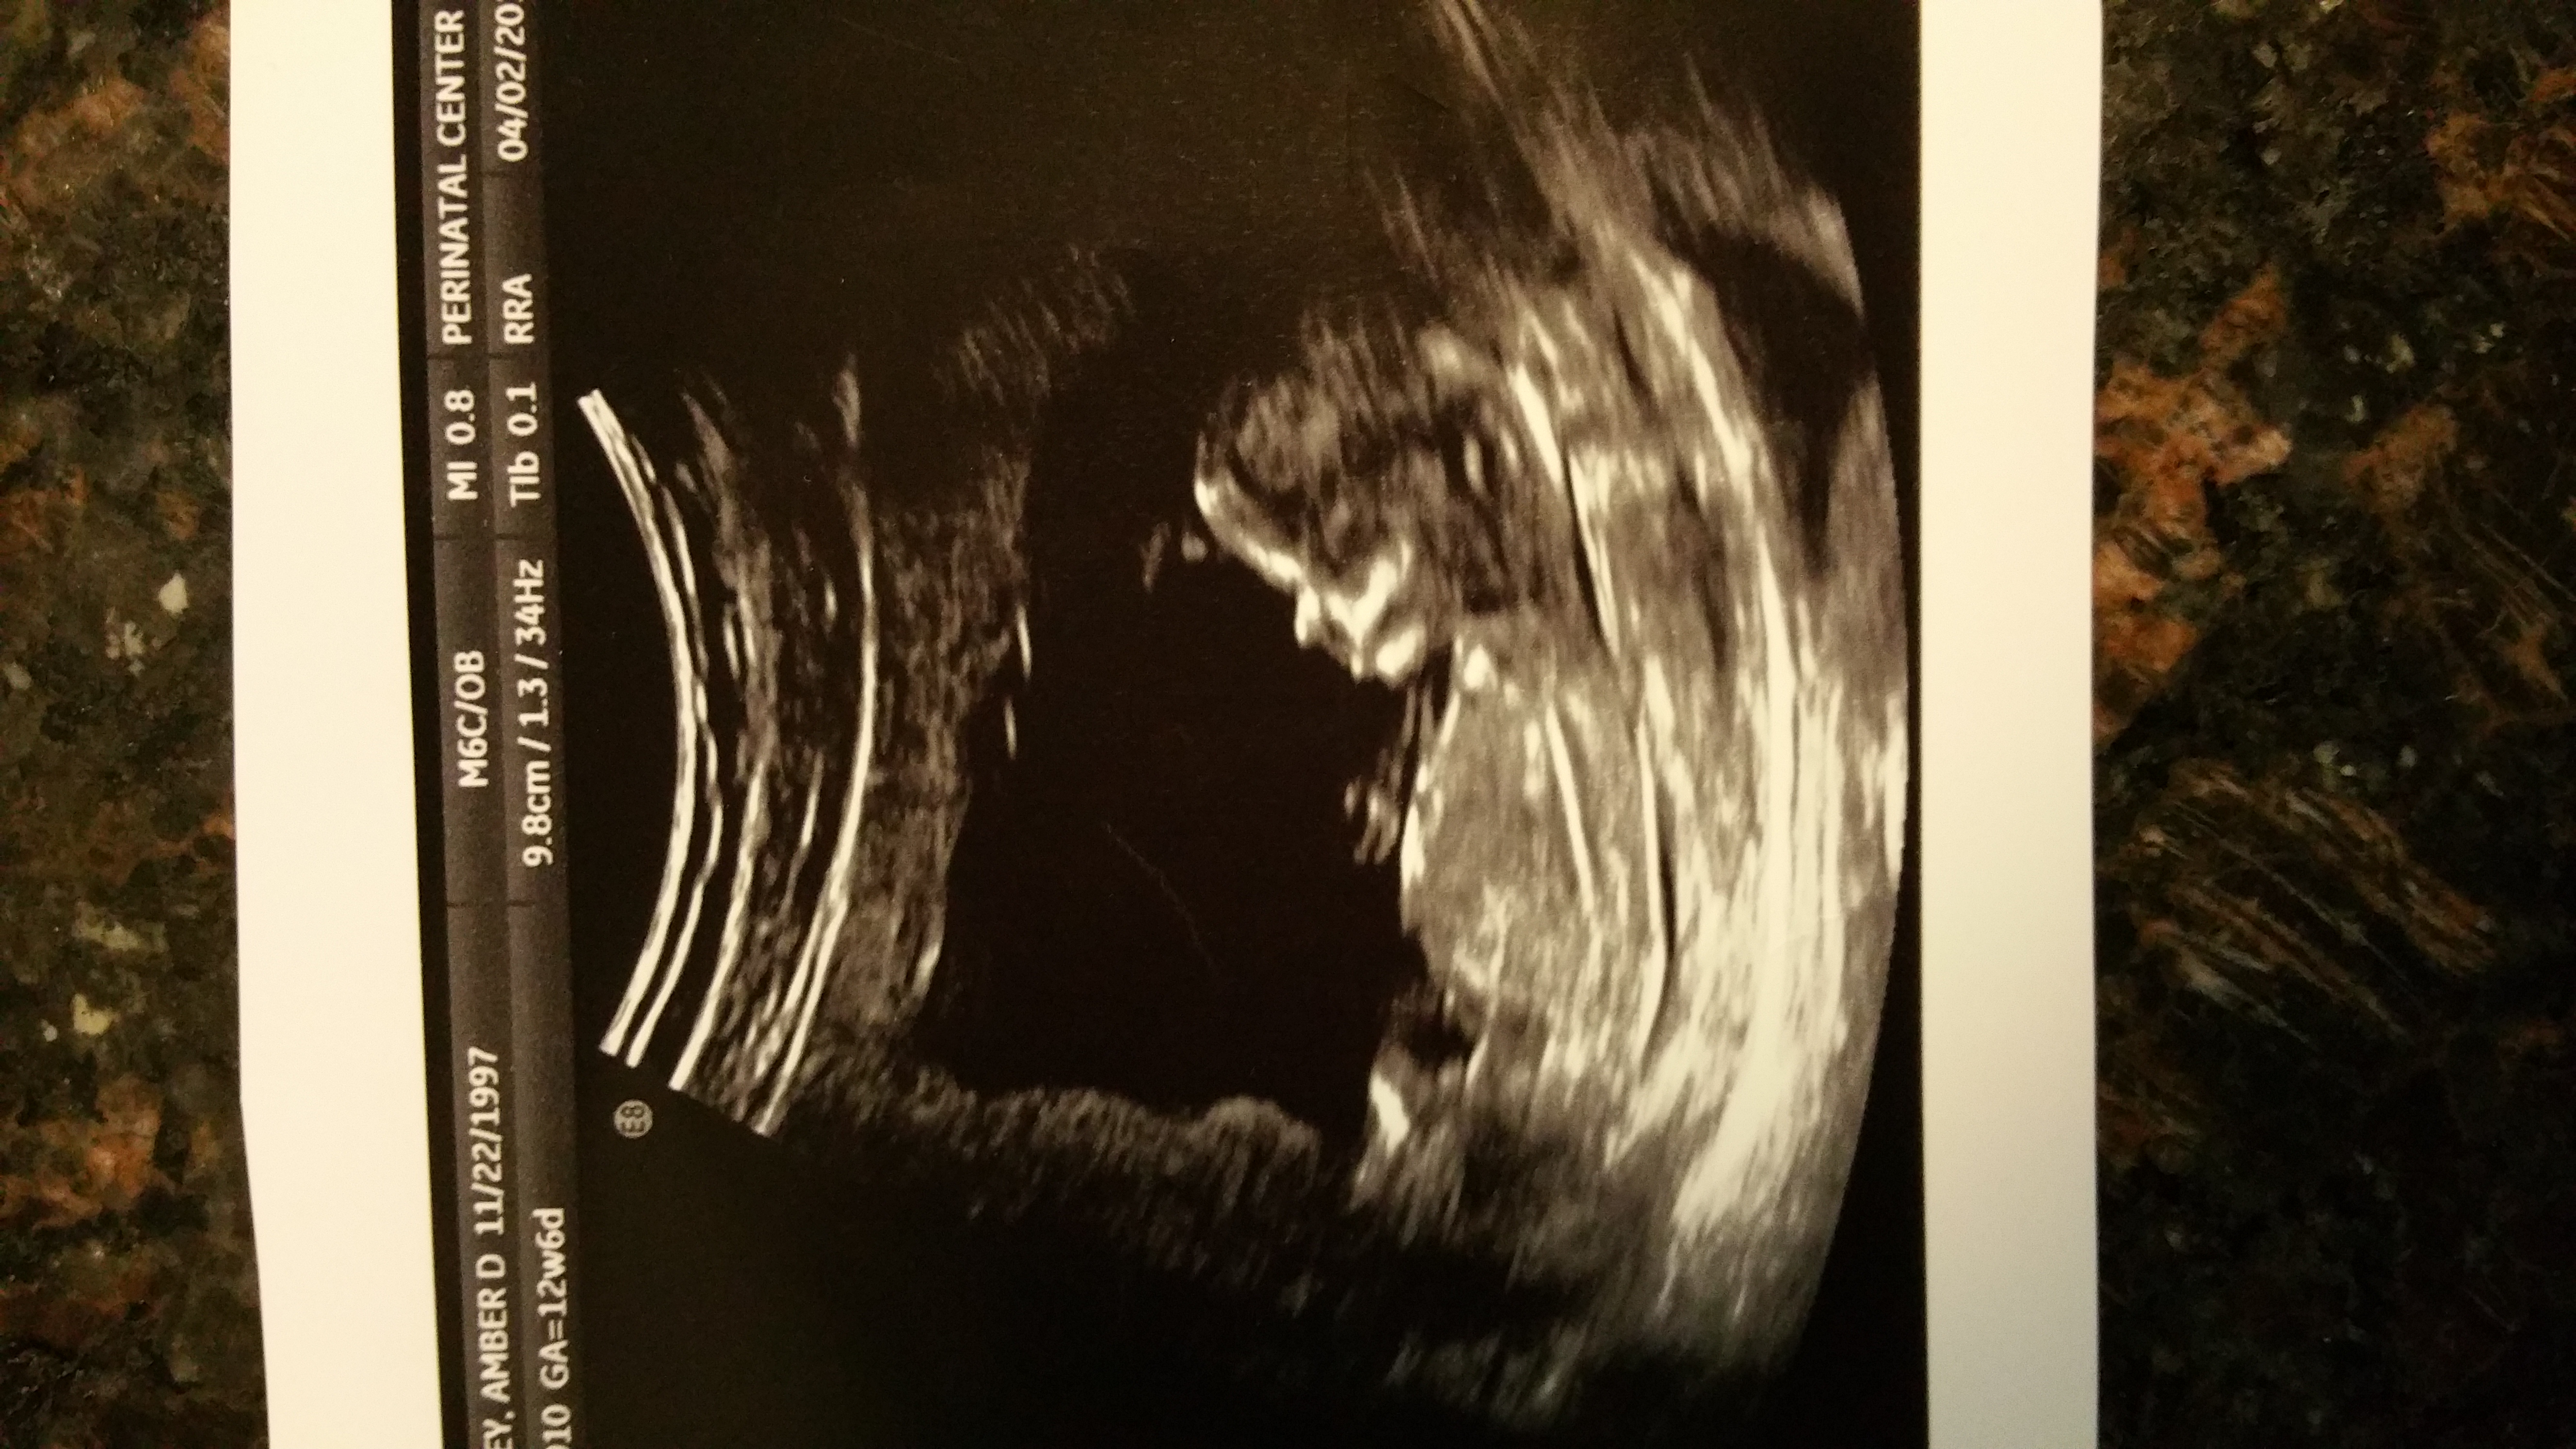

I think girl.

I'm not certain I'm seeing the nub but if it is then I'm leaning boy

Can't see a nub...